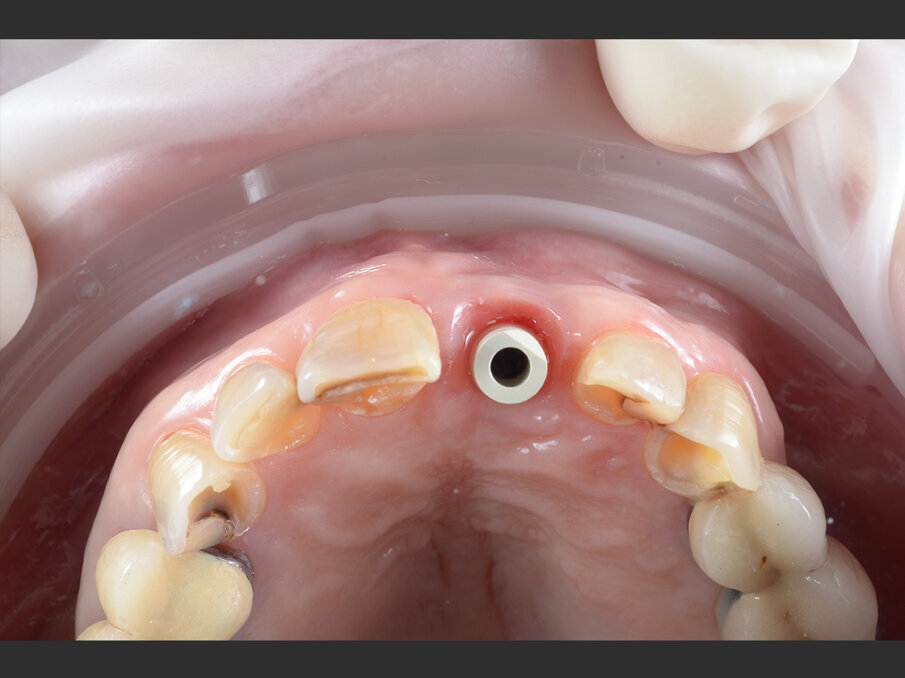

La paziente, donna di 60 anni, non fumatrice ed in buone condizioni di salute generale, si presenta in studio con sintomi di pulpite irreversibile a carico dell’elemento 1.1. L’esame clinico (Figg. 1a, 1b) e radiografico (Fig. 2a) confermano la presenza di una lesione cariosa radicolare che ha colpito il versante mesiale.

Fig. 1b - Valutazione pre-operatoria - visione palatina: è possibile apprezzare la lesione cariosa corono-radicolare.